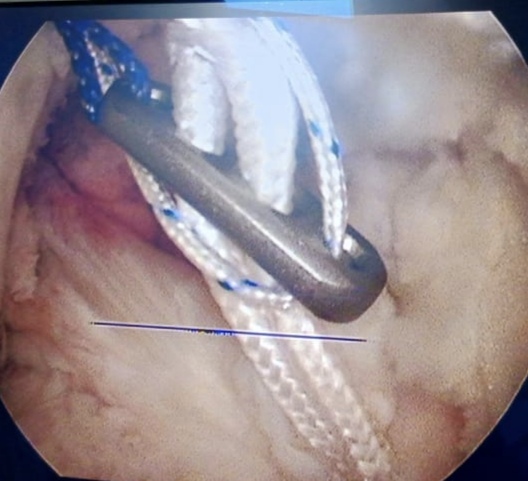

Warning: Graphic Content

The following section contains graphic images of surgical procedures. These images are intended for educational purposes and may be disturbing to some viewers. Viewer discretion is advised.

Surgeries